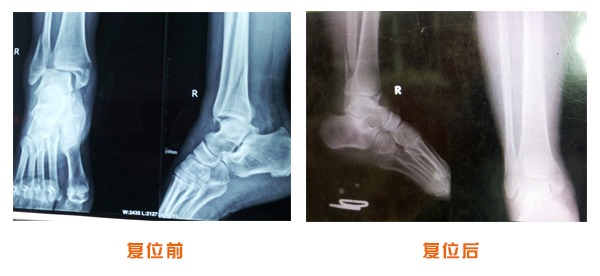

肥城市安駕莊梁氏骨科醫院是一所以梁氏手法正骨配合膏藥為特色的現代化專科醫院。

梁氏骨科術始創于清雍正年間,歷經八代,至今已有三百年歷史。據1929年泰安縣志載“梁瑞圖先生,字增生,號蓮峰,安駕莊人,精岐黃并發(fā)明接骨,凡跌打車凡跌打車軋皮不破而碎骨者......【詳細】 |